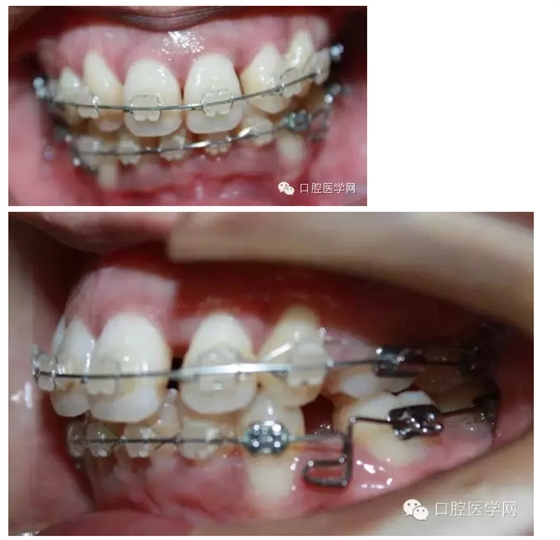

之后我換用0.018x0.025不銹鋼絲,在33,43遠中彎制水平曲,階梯曲,結(jié)果3個月后,效果不明顯,而且牙齒變得有一些不整齊之后我再次用0.016x0.022niti絲,排了一下,在33,43的遠中彎制后傾曲。

最后我用0.016x0.022不銹鋼絲,在33,43遠中彎制水平曲,階梯曲和后傾曲,3個月后,深覆合明顯緩解。

這個病例花了9個月時間,才明顯壓低下前牙,打開咬合。這期間有很多值得我們思考的地方。